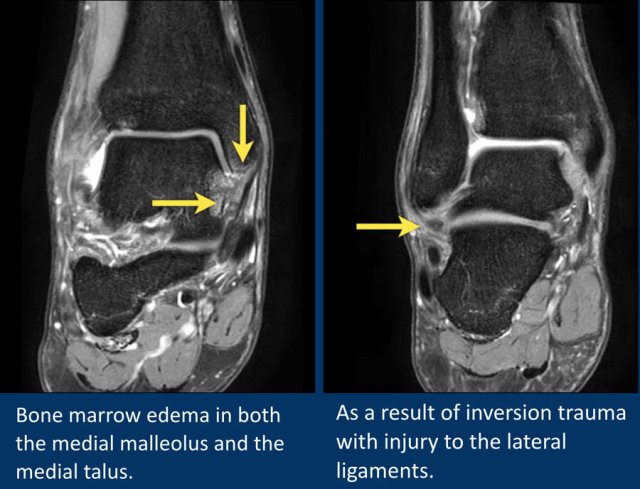

This patient has bone marrow edema in both the medial malleolus and the medial talus.

The lateral ligaments also show edema and thickening.

The bone marrow edema is likely due to impaction of talus and medial malleolus secondary to inversion injury.